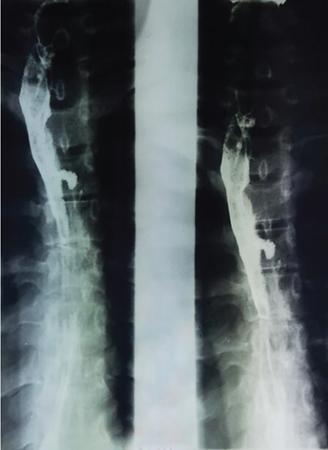

A 60-year-old male with history of chronic alcohol consumption and chronic weight loss and pain epigastrium presented to Radiology for USG. A finding on USG called for a barium meal and follow-through for academic purpose.

Key findings

Barium meal and follow-through spot image revealed widening of C loop of duodenum along with extrinsic compression on the antrum posteroinferiorly giving rise to classical ‘antrum pad’ sign. There was, however, no obvious mucosal irregularity seen. There is evidence of contrast hold-up.

Analysis and interpretation

The image showcases two classical signs in GI radiology which are the ‘widening of C loop of duodenum’ and the ‘antral pad sign’. Both the signs are typically described in masses of head of pancreas. A comment on the mucosal lining (regular/irregular) may give a pointer towards the mass being malignant. However, this is a nonspecific sign giving indication of a mass effect and has a variety of differentials. The final diagnosis is reached with the help of cross-sectional imaging and/or endoscopy/biopsy. CECT abdomen in this case confirmed it to be a case of carcinoma pancreas (Fig. 7.4.6.1).

Image

Fig. 7.4.6.1 CECT showing a mass in the head of pancreas.

Carcinoma head of pancreas

• a) Widening of C loop with irregular mucosal margins.

• b) Antral pad sign.

• c) Frostberg inverted 3 sign.

• d) Definitive diagnosis with CECT.

Fig. 7.4.6.2 Barium meal depicting widened C loop of duodenum.